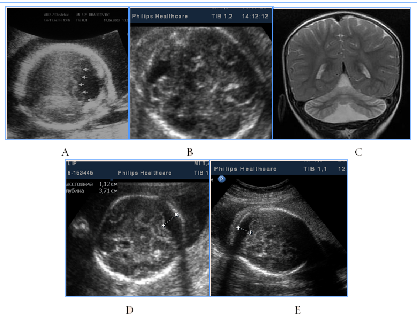

To distress associated antenatal US features of fetal brain could include signs of cortical dysplasia, antenatal intraventricular hemorrhage and PVL (Figure 9) (Figure 10). PVL in the form of small cyst was observed in two fetuses with different premorbid background one fetus with severe prenatal distress and the others with neuroinfection. Particularly attention deserved severe postnatal aftermath of fuzziness and reduced contrast of the fetal brain structures due to cerebral edema and cortical laminar necrosis at 5cases which had different pathogenetic background (Figure 10). Such contrast of structures looked like a result of wrong exposure while getting a picture, but thats were real images, with progression of edema structures looked absolutely "blurred" and cystic PVL lesions were detected. Postnatal catamnesis of all cases was extremely unfavorable.

Figure 9Antenatal distress associated sonographic brain features.

Figure 10Fetal distress associated small-cystic PVL in the fetus and newborn.

A number of fetal intracranial changes as cortical dysplasia, intraventricular hemorrhage, PVL and reduced contrast of the fetal brain structures were observed both in infection and in severe placental dysfunction. Most of such anomalies had periventricular or subependymal localization, which could associated with universal polyetiologic pathogenetic mechanism of the germinal matrix injury. Figure 9 Antenatal distress associated sonographic brain features. A) Revers diastolic flow in the umbilical artery. B). fuzziness and reduced contrast of the fetal brain structures due to cerebral edema on the background of antenatal distress and metabolic acidosis. In clinical catamnesis perinatal loss and extremely severe persistent neurologic morbidity.

Figure 10 Fetal distress associated small-cystic PVL in the fetus and newborn. A) 31 GW, severe IGR, fetal metabolic acidosis, fuzziness and reduced contrast of the brain structures due to cerebral edema, skull deformation due to cortical necrosis, small cysts PVL in the intermediate zone (arrow). B) NSG of the newborn's brain of on the 2nd day of life, progressive small-cystic PVL. Neonatal death.